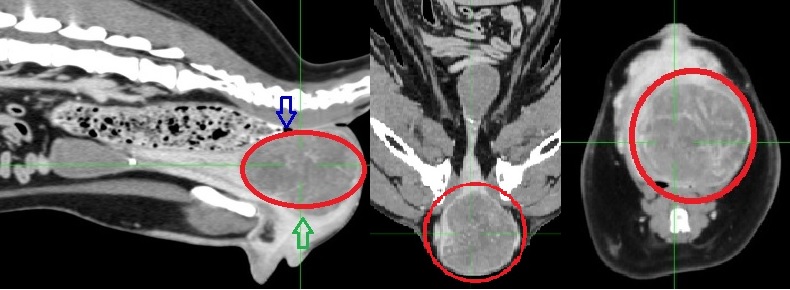

骨盤腔内の膣平滑筋腫のCT画像(赤丸)

腫瘍により直腸(青矢印)と尿道(緑矢印)が圧迫されている